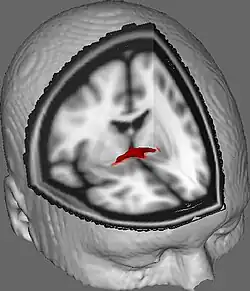

La commissure antérieure, appelée également la commissure blanche antérieure ou encore la précommissure (en latin : commissura anterior), est une commissure inter-hémisphérique qui croise transversalement la paroi antérieure du troisième ventricule[1]. C'est un faisceau nerveux de substance blanche (un paquet d'axones) qui relie les deux lobes temporaux des hémisphères cérébraux à travers la ligne médiane, et il se trouve en avant des colonnes du fornix (les piliers antérieurs trigone du cerveau). Chez la plupart des mammifères existants, la grande majorité des fibres reliant les deux hémisphères traversent le corps calleux, qui est plus de 10 fois plus grand que la commissure antérieure, et d'autres voies de communication passent par la commissure de l'hippocampe ou indirectement, via des connexions sous-corticales. Néanmoins, la commissure antérieure est une voie importante qui peut être distinguée clairement dans les cerveaux de tous les mammifères.

Dans une section sagittale, la commissure antérieure est de forme ovale, ayant un long axe vertical qui mesure environ 5mm.